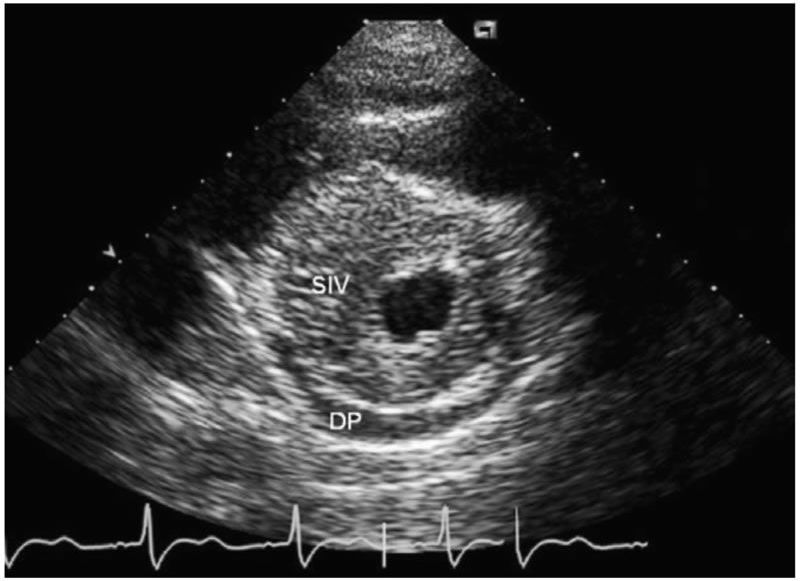

¿Cómo es una miocardiopatía hipertrófica? ¿Qué tipos existen? buff.ly/2yDwY4O Repaso del capítulo "Miocardiopatías" de nuestra Biblioteca de Preguntas Básicas de Imagen Cardíaca

¿Cómo es una miocardiopatía hipertrófica? ¿Qué tipos existen? buff.ly/2yDwY4O

Repaso del capítulo "Miocardiopatías" de nuestra Biblioteca de Preguntas Básicas de Imagen Cardíaca